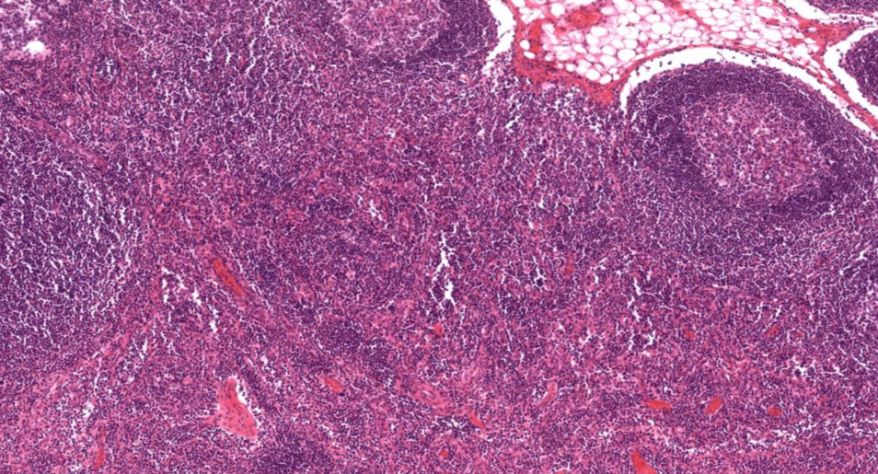

低倍镜:胸腺表面包有薄层结缔组织构成的被膜,结缔组织深入实质,将胸腺分成许多不完整的小叶。每个小叶分为周围的皮质和中央的髓质两部分。皮质中胸腺细胞排列密集,故染色深;髓质中胸腺细胞较少,胸腺上皮细胞多,故染色浅,其中可见染成红色的圆形小体-胸腺小体。高倍镜:胸腺小体大小不等,由几层至十几层扁平的胸腺上皮细胞呈同心圆状排列而成,其外周的细胞较幼稚,细胞核明显;小体中央部分的上皮细胞已退化,细胞核消失,胞质呈均质状,染成红色。

1.成人胸腺全景图

2.被膜

3.皮质

4.髓质